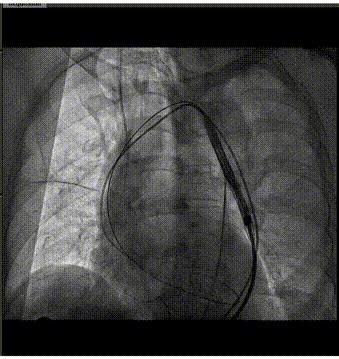

手术过程概览

主动脉根部造影

导丝跨瓣

球囊预扩

输送器过弓

输送器定位

瓣膜定位

瓣膜脱钩

瓣膜位置非常理想,并稳定锚定。